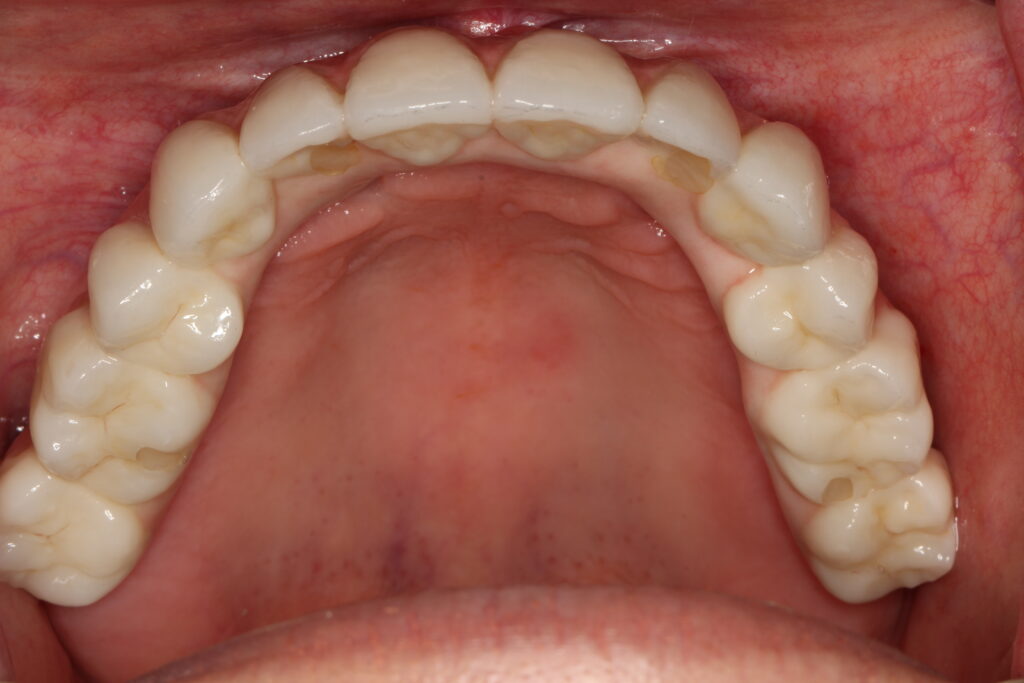

A selection of full arch fixed implant bridge patients after 5 years of wear